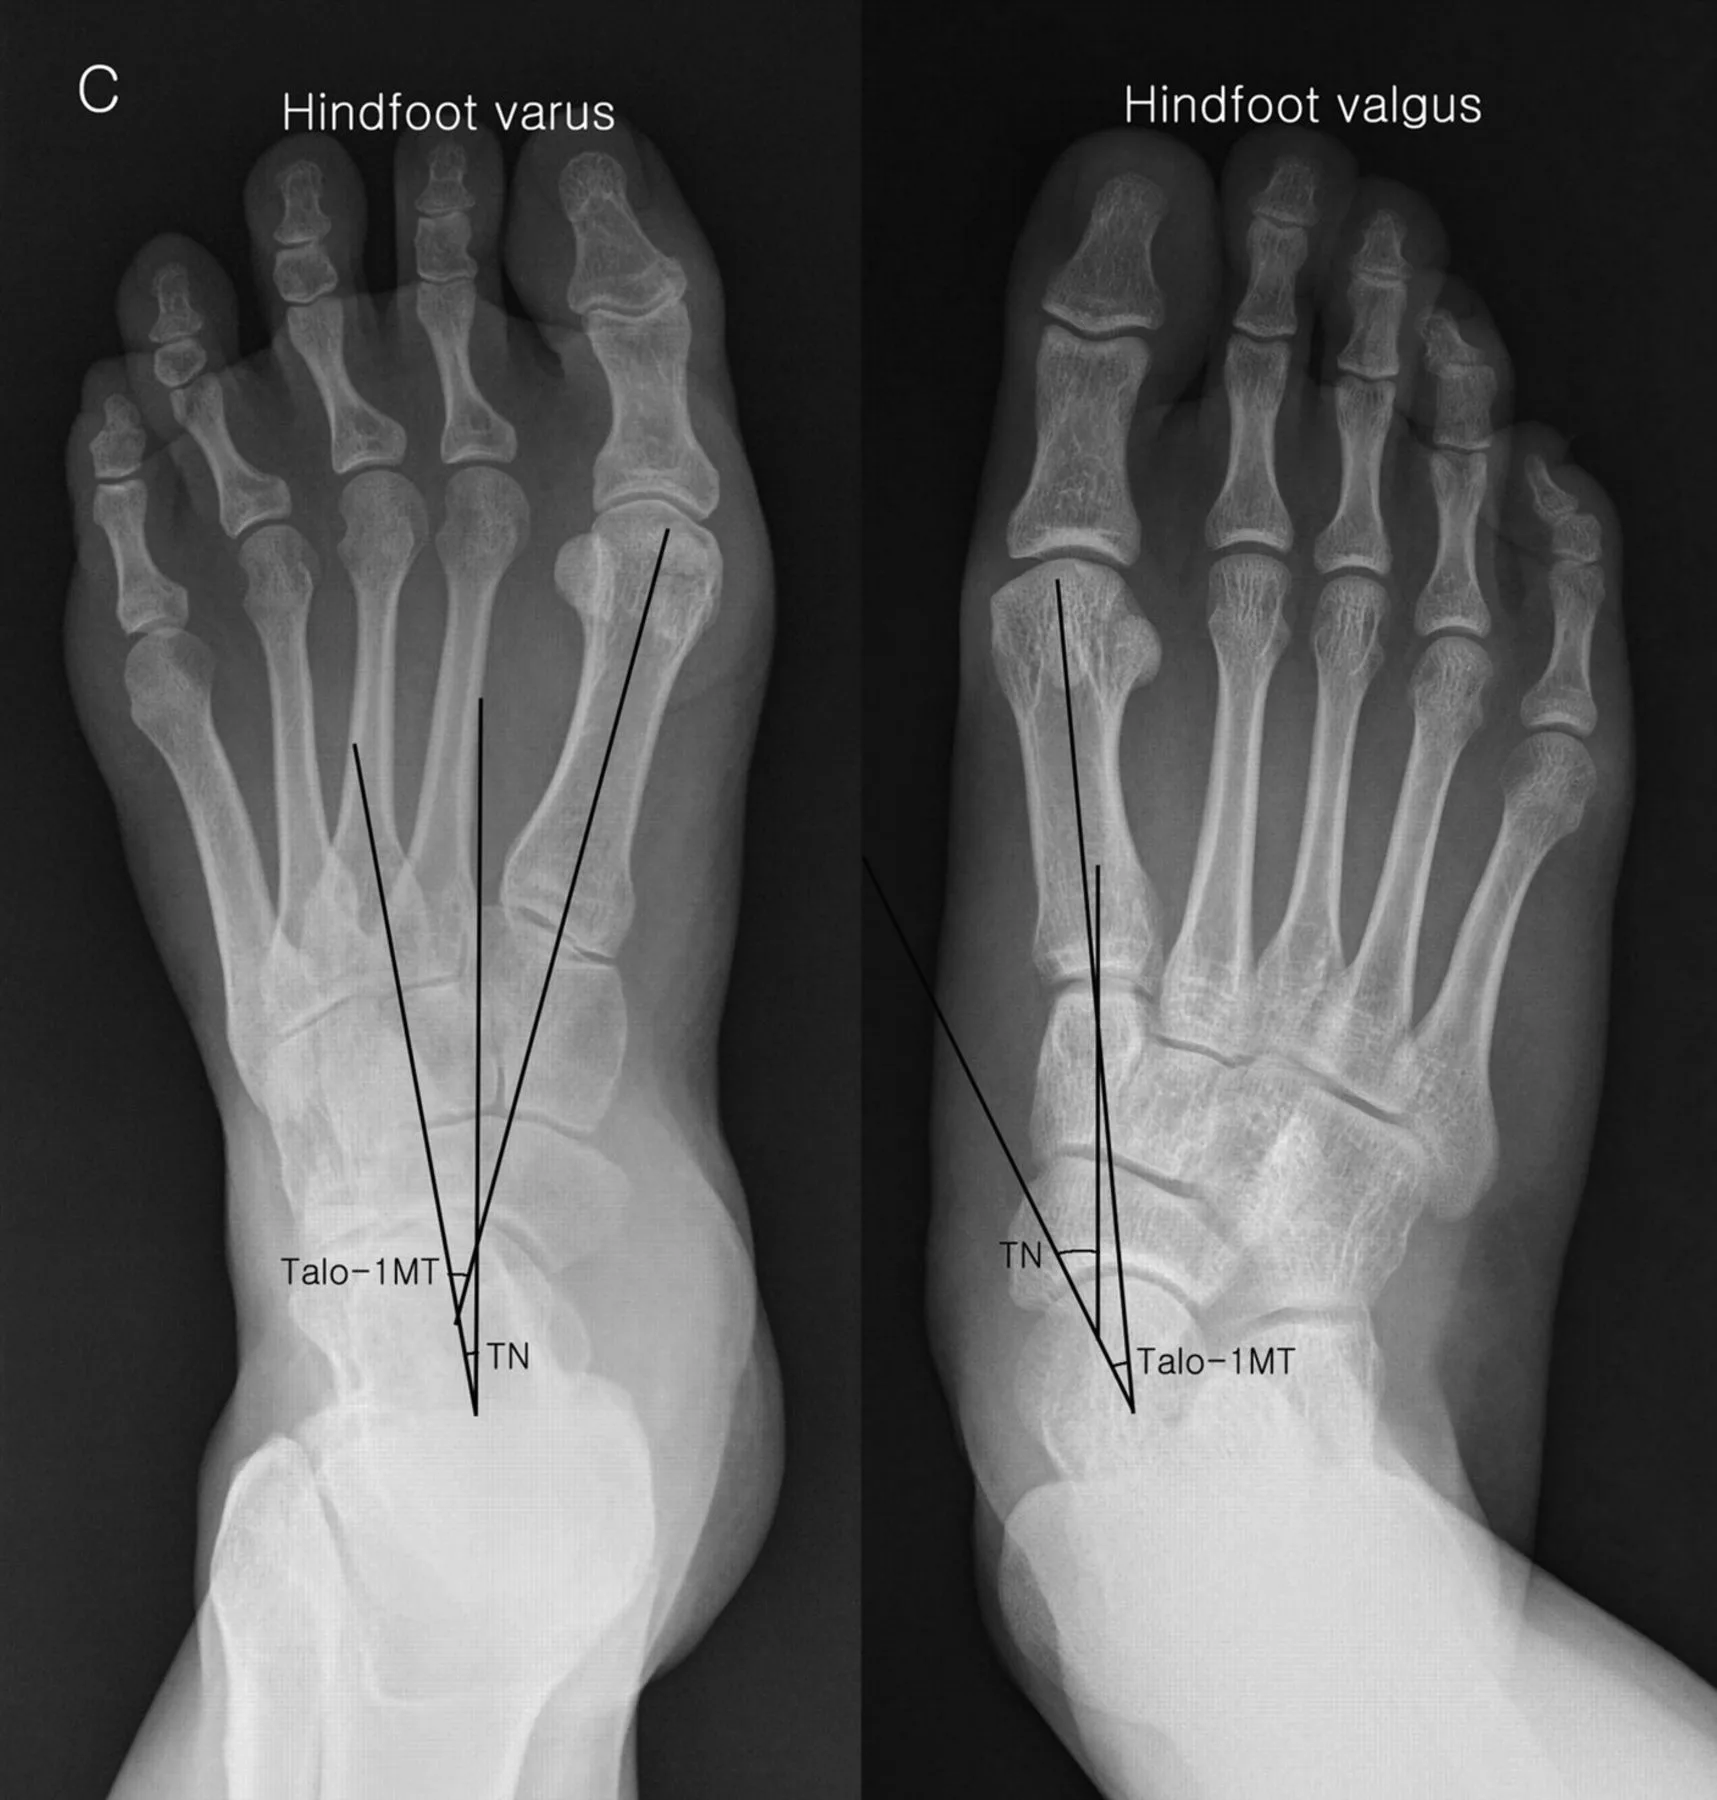

Диагностика вальгусной деформации

Составляющие диагностики вальгусной деформации стоп:

- инструментальные исследования – рентгенография стоп, плантография, подометрия;